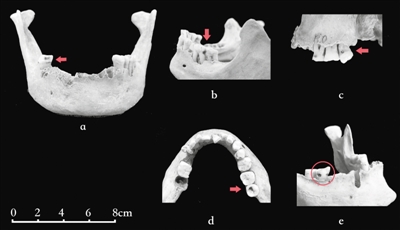

古代人骨标本患龋情况示意图受访者供图

现代流行病学常用患龋率(在一定时间内特定人群中患龋人数占总人口基数的百分比)来对现代人龋病情况进行统计。而由于发掘出土的人骨标本的颌骨常常破损,特别是墓葬中散落的牙齿有时很难准确复位到齿槽内,因此研究人员通常根据龋齿数占观察总齿数的百分比来了解古人群龋病情况。